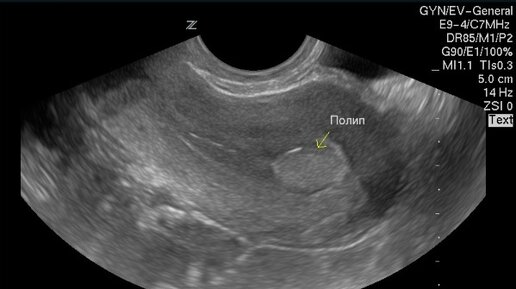

Гинекологическое ультразвуковое исследование (УЗИ) – это безопасная процедура, позволяющая врачу получить детальное представление о состоянии женских органов. Цели гинекологического УЗИ 1. Диагностика заболеваний УЗИ позволяет выявить различные гинекологические заболевания: ● Миома матки ● Киста яичников ● Эндометриоз ● Полипы 2. Контроль за беременностью УЗИ является важной процедурой для контроля за развитием плода, состоянием матки во время беременности. 3. Оценка фолликулогенеза УЗИ помогает...